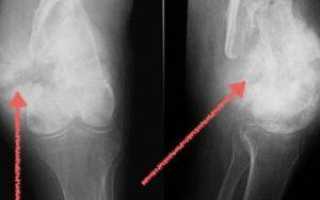

Артроз

Это разрушение хрящевой ткани в коленном суставе и образование остеофитов, то есть костных наростов. Артроз приводит к деформации, сужению суставной щели и образованию анкилоза. Постепенно, если не проводить лечение, щель между суставами полностью исчезает, и подвижность сустава теряется.

Артроз может развиваться у людей любого возраста. На начальном этапе заболевание протекает незаметно, и боль ощущается лишь после значительных физических нагрузок, после чего она проходит самостоятельно.

На второй стадии болевые ощущения становятся постоянными, и человеку требуется принимать обезболивающие и противовоспалительные препараты. Из-за боли амплитуда движений в колене значительно уменьшается.

На последней стадии происходит полное разрушение хрящевой ткани. Пациент страдает от постоянных болей и теряет возможность нормально передвигаться, в данной ситуации единственным решением может стать операция.